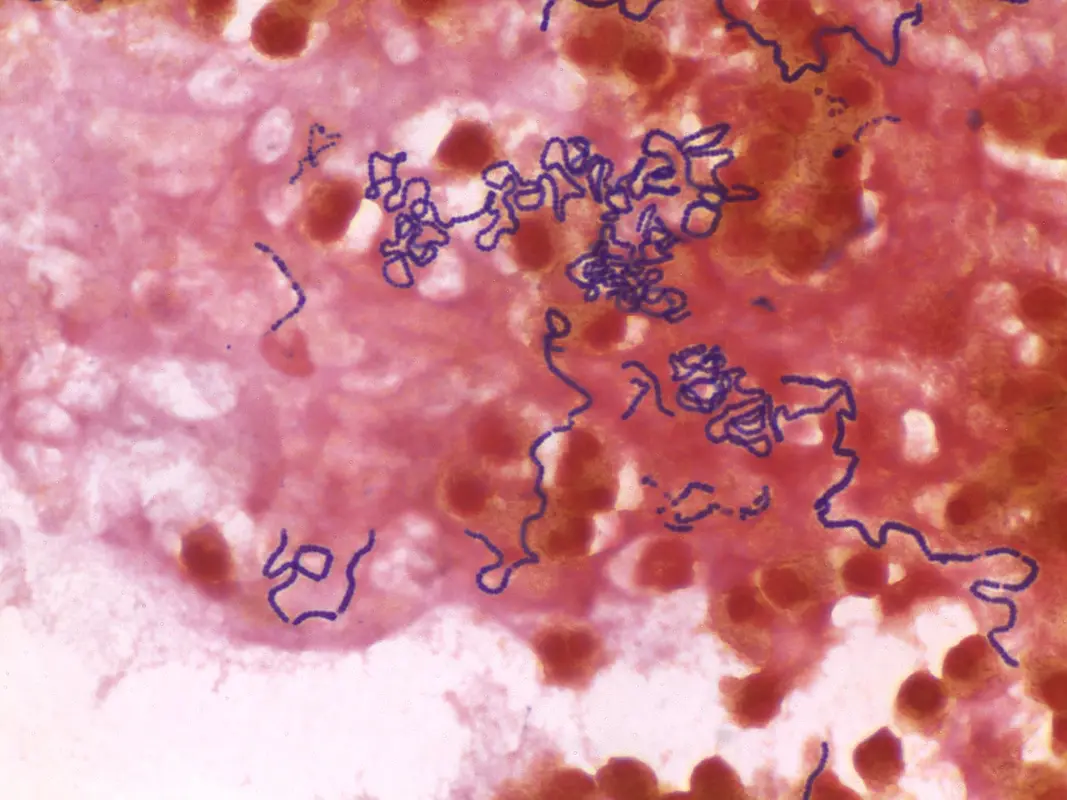

Группа Streptococcus anginosus (SAG) состоит из трех отдельных видов: Streptococcus anginosus (S. anginosus), Streptococcus intermedius (S. intermedius) и Streptococcus constellatus (S. constellatus).

Эти виды обычно обитают на различных слизистых оболочках, включая полость рта, ротоглотку, дыхательные пути, желудочно-кишечный тракт и мочеполовую систему, и признаны наиболее распространенными возбудителями абсцессов мозга, абсцессов печени и эмпиемы плевры. Несмотря на их медицинскую значимость, в литературе наблюдается значительный недостаток сведений о возбудителях SAG. Растущее число сообщений о случаях угрожающих жизни инфекций, вызванных SAG, свидетельствует о его новой патогенности. Последние клинические данные свидетельствуют о существовании таких инфекций, характеризующихся формированием различных видов эмпиемы и абсцессов.

Инфекция S. intermedius может вызывать абсцессы в различных органах, причем наиболее часто встречаются абсцесс головного мозга и абсцесс печени. Другие проявления включают абсцесс легких, некротизирующую пневмонию, внутрибрюшинные инфекции, бактериемию и инфекционный эндокардит, гнойный перикардит, остеоартикулярные инфекции, инфекции позвоночника и редко - синдром Лемьера (интраяремный венозный септический тромбофлебит).